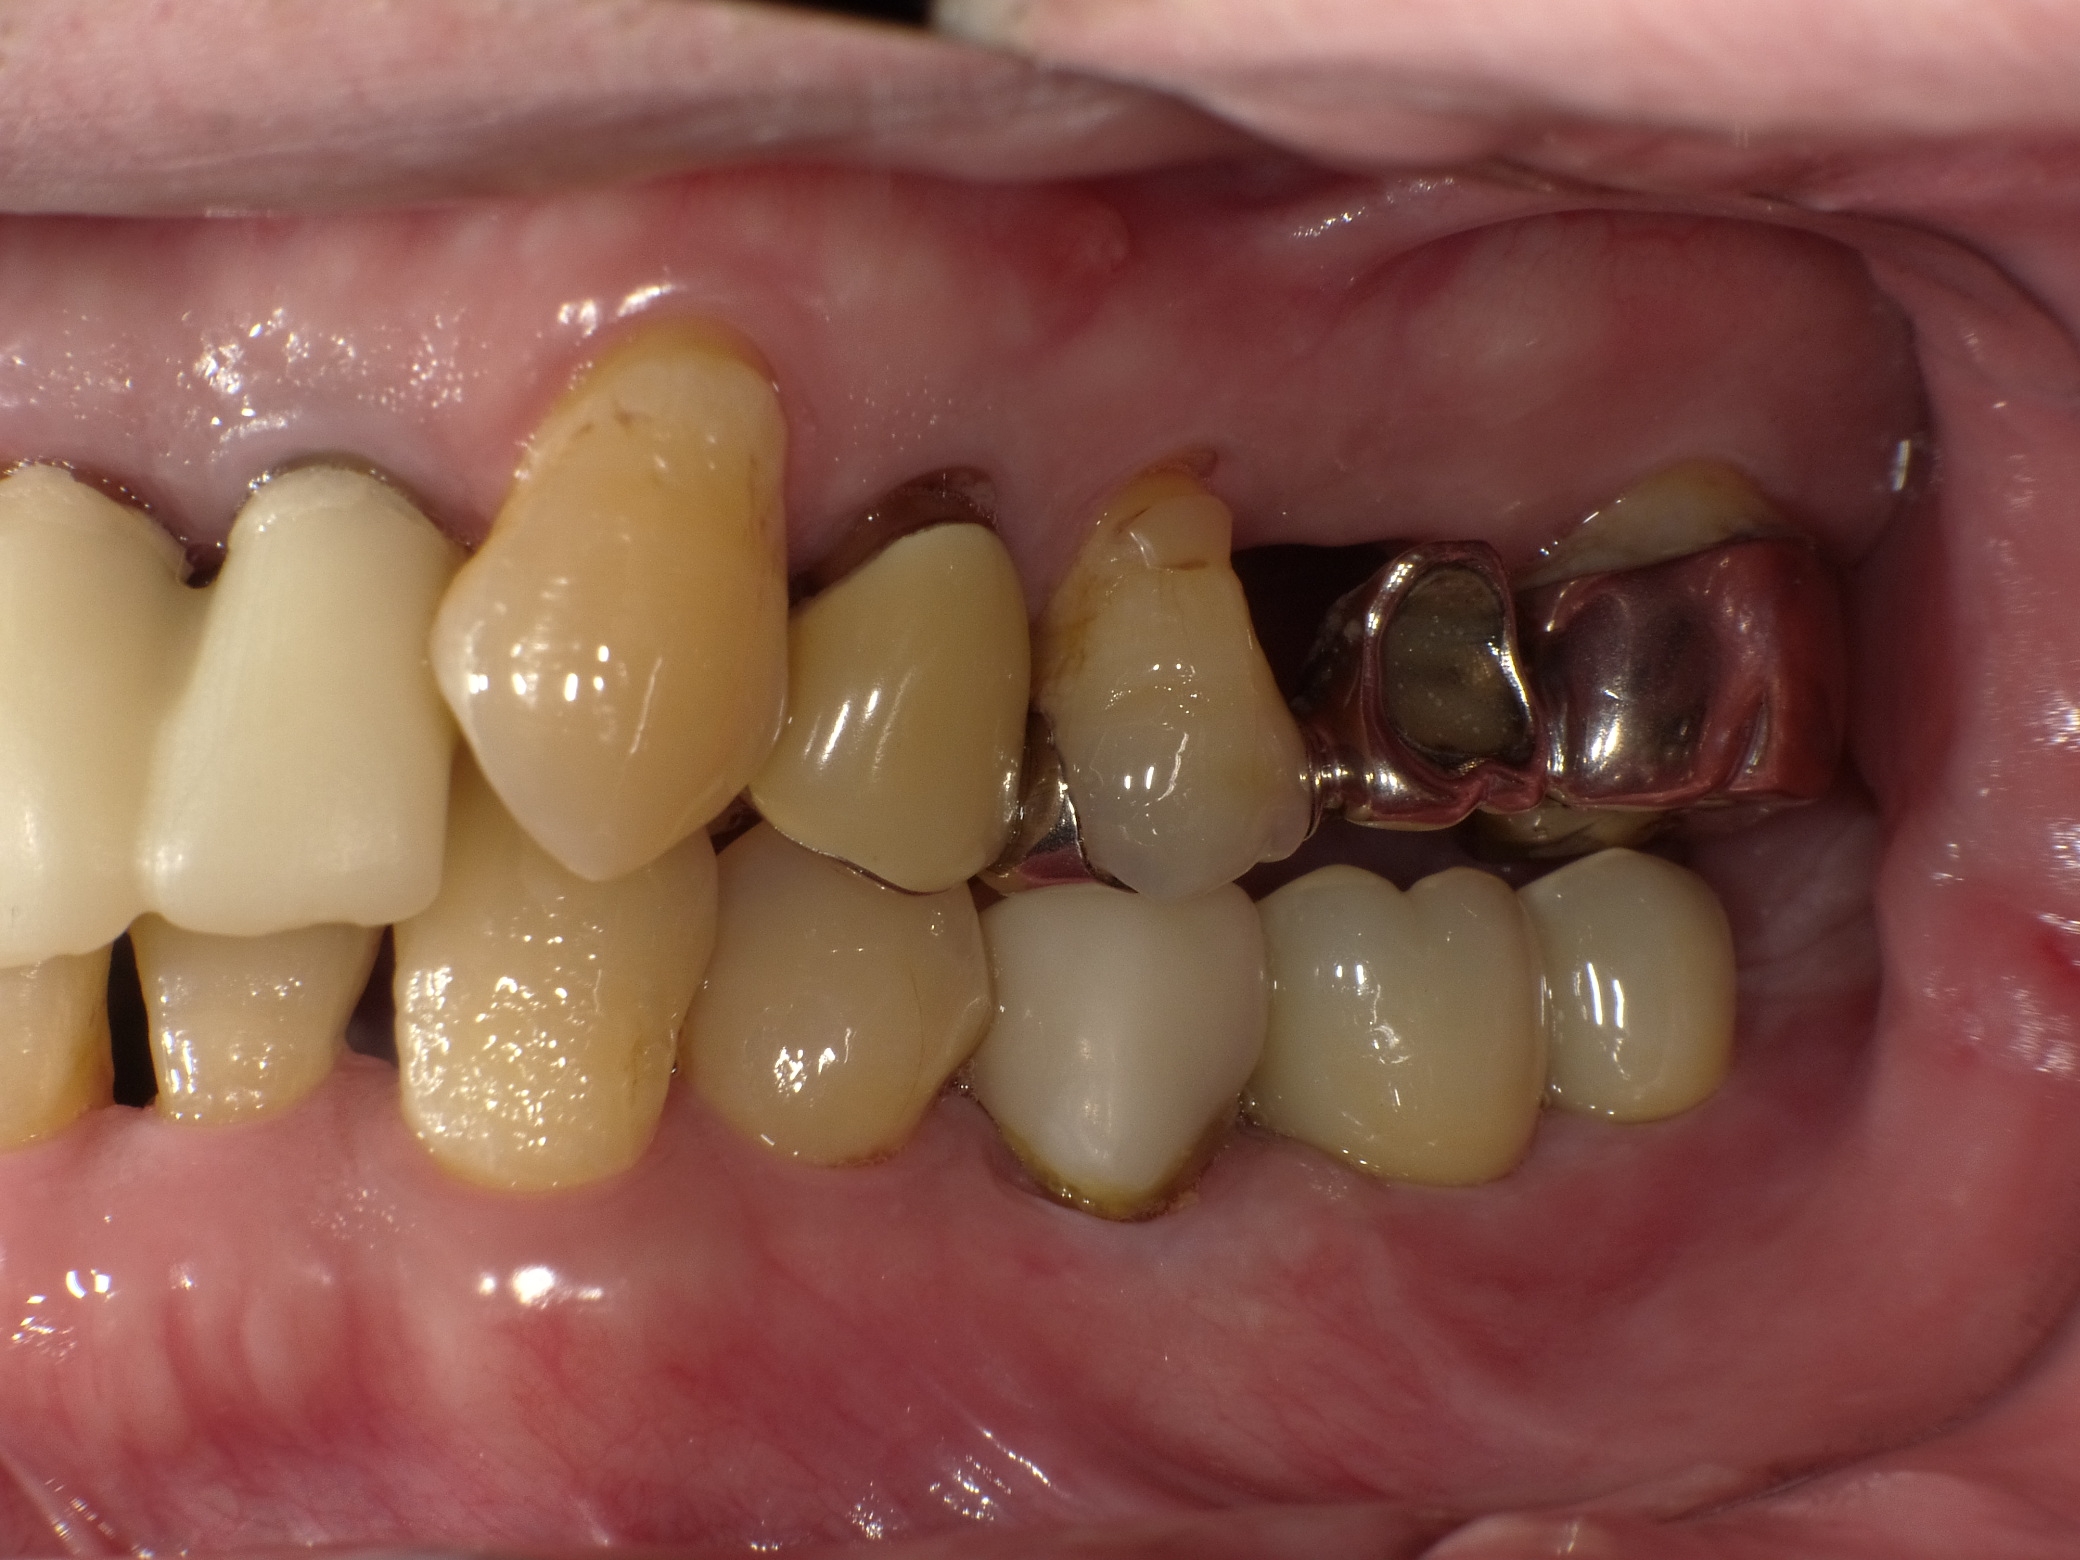

インプラントオーバーデンチャー症例

主訴 しっかり噛んで美味しいものを食べたい(男性) 治療内容 保存不可能な歯を抜歯後、2本のインプラントを埋入。

インプラントのアタッチメントと入れ歯の留め具とで凹凸接続し、動かない快適な入れ歯を装着しています。治療期間 約4ヶ月 費用 総額 ¥880,000–(税込) リスクと副作用 ・外科治療となるので、お身体の状態によっては受けれない場合がある(広範囲に適用可能な治療ですが、個々の患者様の状況によって適用外な場合もある)

・術後に多少の痛みや腫れが出ることがある

-